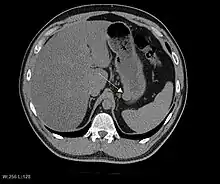

CT image of a GIST in the gastric cardia. The lesion appears submucosal, is hypervascular and protrudes intraluminally. Upper GI bleeding led to endoscopy, finding an ulcerated mass.

As the tumor grows it may project outside the bowel (exophytic growth) and/or inside the bowel (intraluminal growth), but they most commonly grow exophytically such that the bulk of the tumor projects into the abdominal cavity. If the tumor outstrips its blood supply, it can necrose internally, creating a central fluid-filled cavity with bleeding and cavitations that can eventually ulcerate and communicate into the lumen of the bowel. In that case, barium swallow may show an air, air-fluid levels or oral contrast media accumulation within these areas.[14][17] Mucosal ulcerations may also be present. In contrast-enhanced CT images, large GISTs appear as heterogeneous masses due to areas of living tumor cells surrounding bleeding, necrosis or cysts, which is radiographically seen as a peripheral enhancement pattern with a low attenuation center.[13] In MRI studies, the degree of necrosis and bleeding affects the signal intensity pattern. Areas of bleeding within the tumor will vary its signal intensity depending on how long ago the bleeding occurred. The solid portions of the tumor are typically low signal intensity on T1-weighted images, are high signal intensity on T2-weighted images and enhanced after administration of gadolinium. Signal-intensity voids are present if there is gas within areas of necrotic tumor.[15][18][19]

Features of malignancy

Malignancy is characterized by local invasion and metastases, usually to the liver, omentum and peritoneum. However, cases of metastases to bone, pleura, lungs and retroperitoneum have been seen. In distinction to gastric adenocarcinoma or gastric/small bowel lymphoma, malignant lymphadenopathy (swollen lymph nodes) is uncommon (<10%) and thus imaging usually shows absence of lymph node enlargement.[13] If metastases are not present, other radiologic features suggesting malignancy include: size (>5 cm), heterogeneous enhancement after contrast administration, and ulcerations.[4][13][20] Also, overtly malignant behavior (in distinction to malignant potential of lesser degree) is less commonly seen in gastric tumors, with a ratio of behaviorally benign to overtly malignant of 3-5:1.[4] Even if radiographic malignant features are present, these findings may also represent other tumors and definitive diagnosis must be made immunochemically.